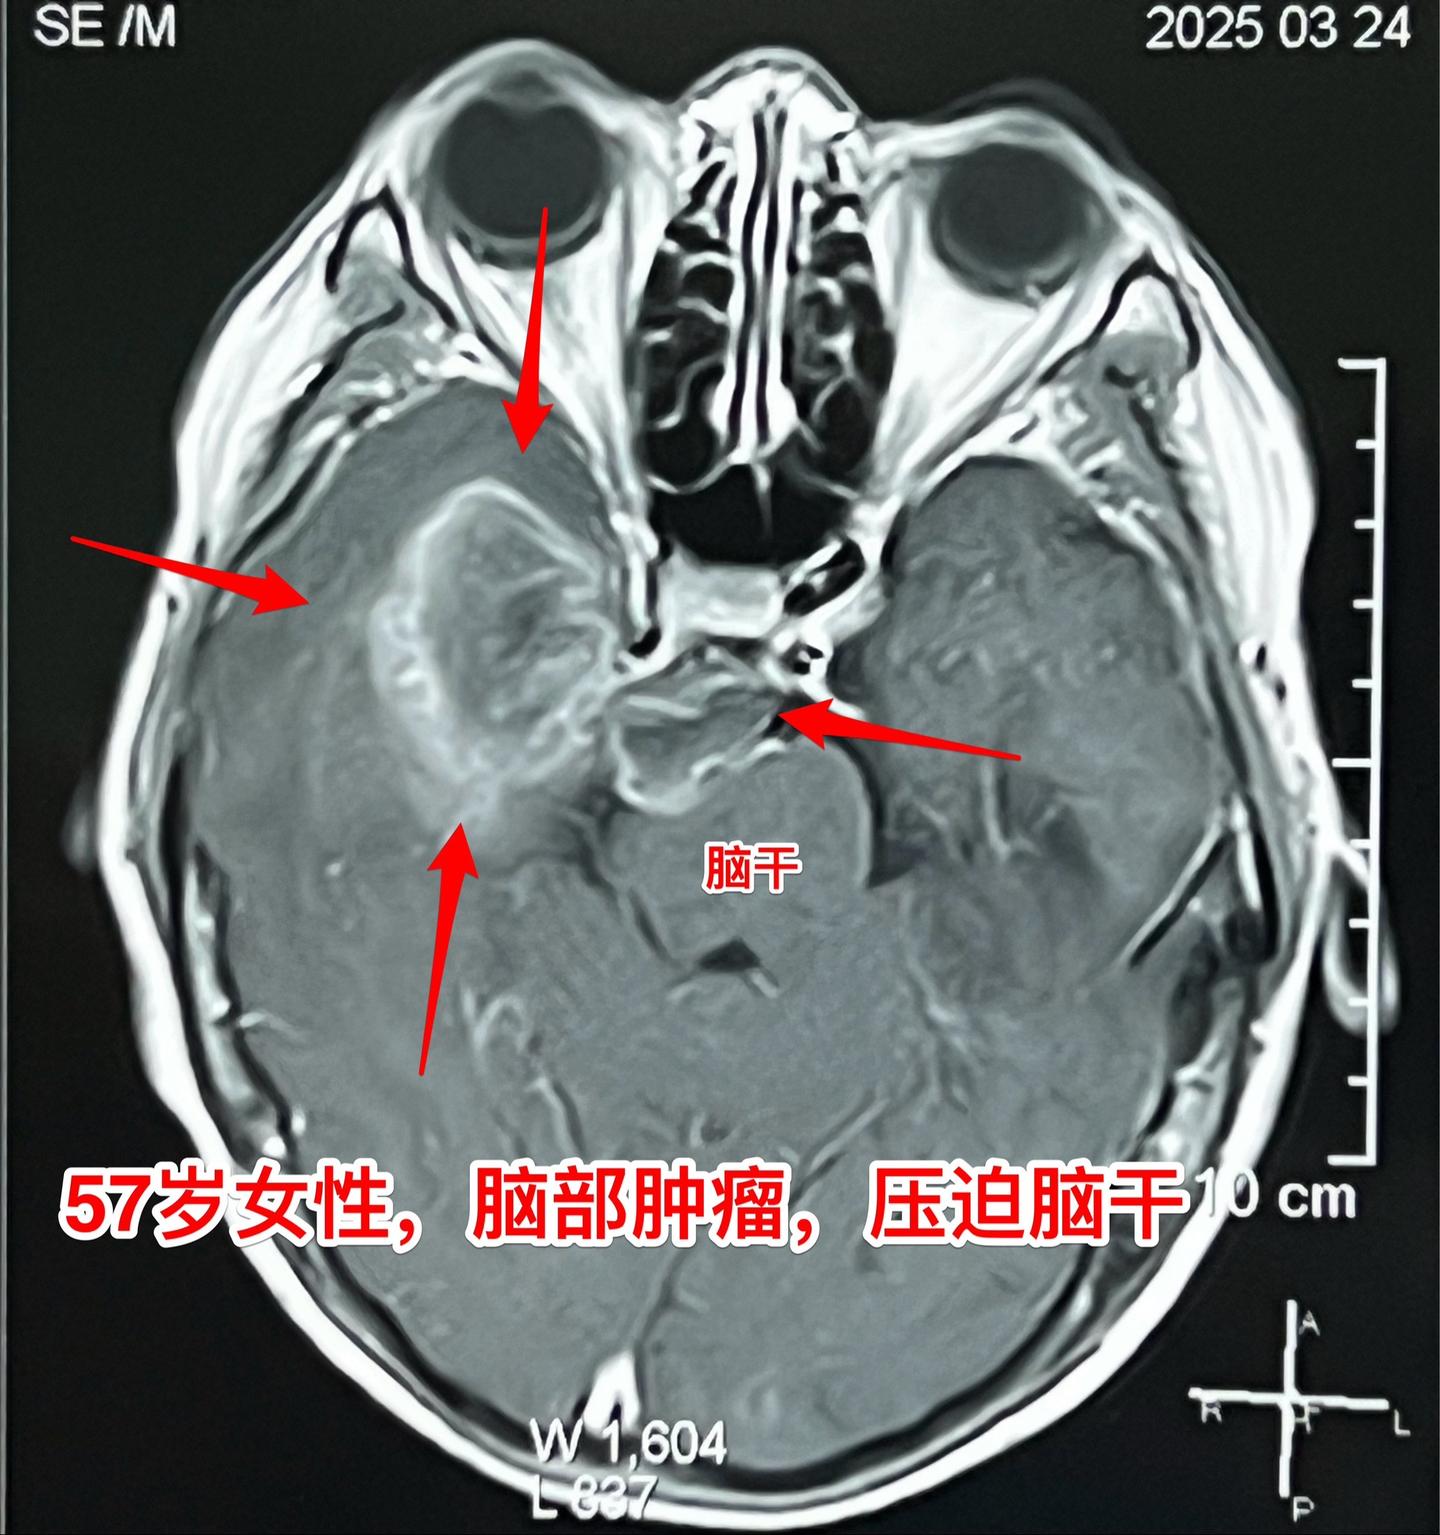

肺癌患者多年后出现脑部转移。57岁的韶关女病人在18年前患肺癌,作了手术切除肺癌并作了化疗,随后多次复查,没有发现肿瘤复发。她也在正常上班。 就在这个春节前她的婆婆去世了,她的情绪似乎受到严重影响,和平时不一样,总是担惊受怕。 三月份经家人提醒,到当地医院去作头部CT检查,结果发现脑部有个瘤,像鸡蛋那么大了!医生怀疑是胶质瘤。 3月22日到北京来找我住院。3月27日晚作了手术,手术中看见肿瘤形态符合肺癌脑转移。等待病理报告。